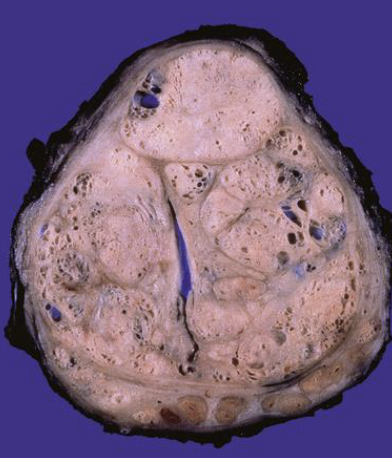

prostate cancer

the following describes the histopathology of what condition?

• Adenocarcinoma- glandular formation, lined by single layer of cuboidal or columnar epithelium

• Glands are smaller & crowded than benign prostate

• Basal cells not seen

prostate cancer adenomocarcinoma